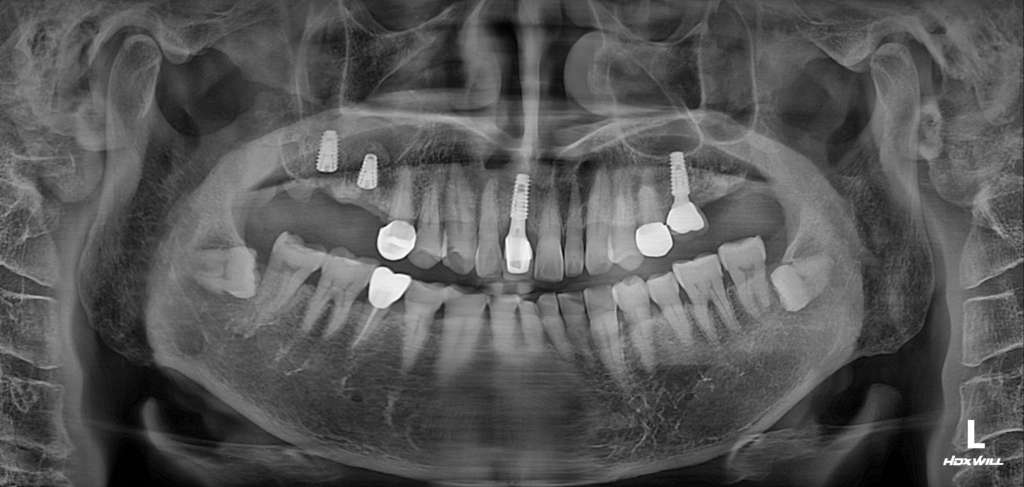

25.04.07